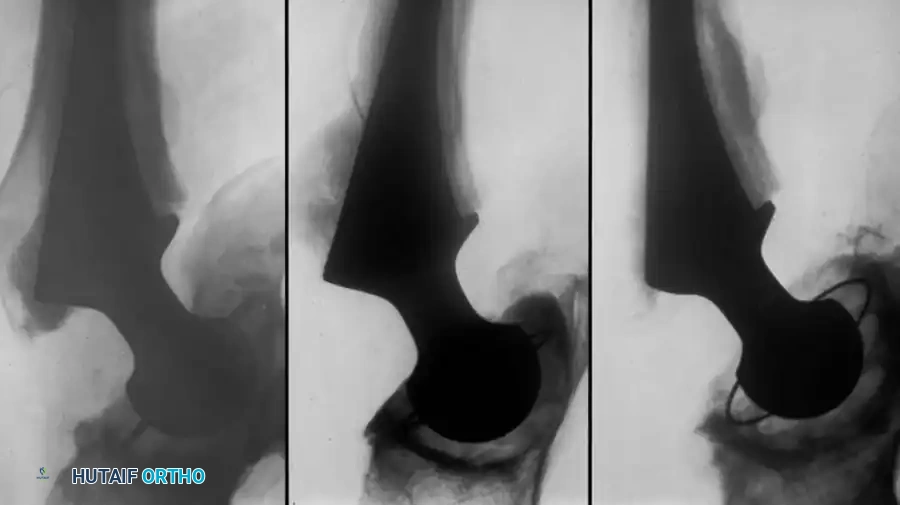

Associated Surgical & Radiographic Imaging